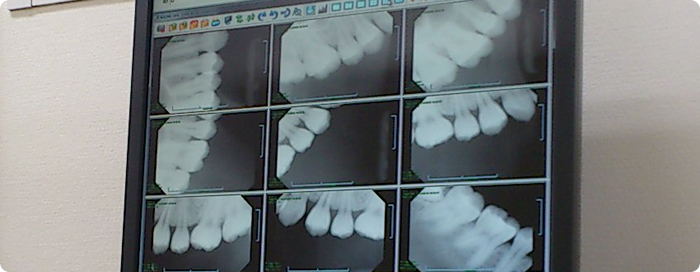

デジタルレントゲン

Digital X-ray

当院では、患者さまにも環境にもやさしいデジタルレントゲンを導入しています。

デジタルレントゲン撮影は従来のフィルムを使うレントゲンに比較して、少ないX線量で撮影ができるので、 被ばく量をかなり軽減できるなど様々な利点があります。